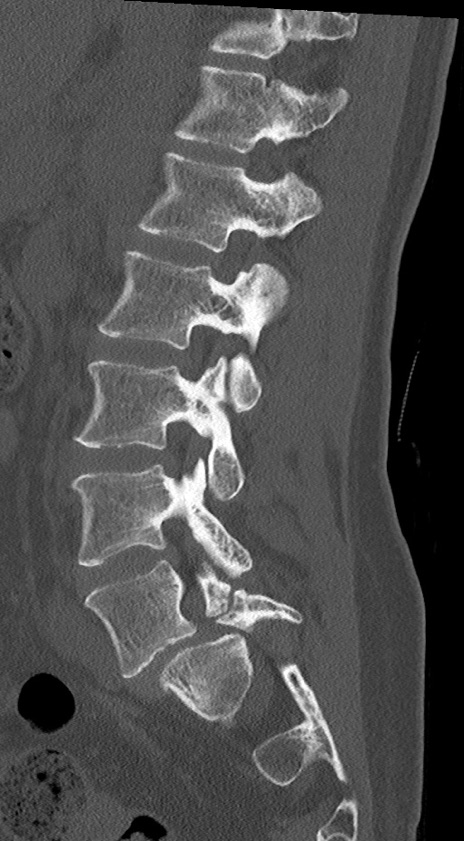

腰椎CT

横断像

冠状断像